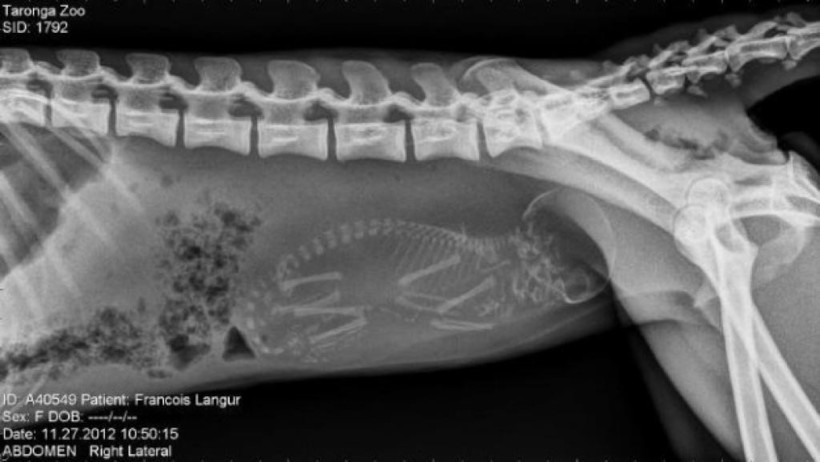

Обезьяна